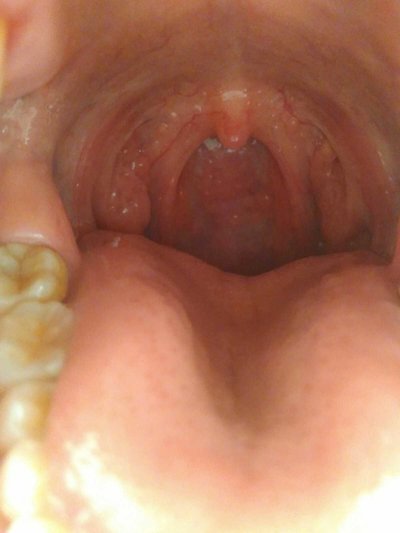

Cough is the sound of breathing in quickly and exhaling strongly when the mucous membrane of larynx or trachea is stimulated, and the vocal cord vibrates. Cough is the defensive reflex of the respiratory system, which is conducive to the removal of respiratory secretions and harmful factors. How is cough treated? Let's talk about it